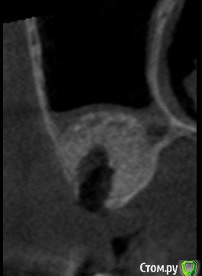

Andre_ Опубликовано 14 июня, 2018 Поделиться Опубликовано 14 июня, 2018 ... в чём дело, сразу не поймёшь.Добрый всем день. Выполнен открытый синус - лифтинг с Bio-Oss, исходно в области альвеолярного отростка высота своей кости 2-3 мм, через 6 месяцев - имплантация без особенностей, ложе умеренно кровило. Гранулы на сверле были, но встали имплантаты с торком порядка 20 Н/см2. Раскрытие спустя 3 мес., имплантаты на фдм выкручены рукой. Ложа откюретированы, заполнены коллагеном и ушиты, спустя 5 суток жалобы на боли - искомая область абсцедирует. Разрез, гной и крупицы, стенки и дно ложа винтов при зондировании инструментом таки твёрдые. Назначены а\б повторно, и загружены фото с контрольной КТ. Где, по- вашему, допустио ошибку и какую? И каков прогноз на переустановку? Столкнулся с такой проблемой впервые и немного дезориентировался. Ссылка на комментарий

TIGER Опубликовано 20 июня, 2018 Поделиться Опубликовано 20 июня, 2018 ... в чём дело, сразу не поймёшь.Добрый всем день. Выполнен открытый синус - лифтинг с Bio-Oss, исходно в области альвеолярного отростка высота своей кости 2-3 мм, через 6 месяцев - имплантация без особенностей, ложе умеренно кровило. Гранулы на сверле были, но встали имплантаты с торком порядка 20 Н/см2. Раскрытие спустя 3 мес., имплантаты на фдм выкручены рукой. Ложа откюретированы, заполнены коллагеном и ушиты, спустя 5 суток жалобы на боли - искомая область абсцедирует. Разрез, гной и крупицы, стенки и дно ложа винтов при зондировании инструментом таки твёрдые. Назначены а\б повторно, и загружены фото с контрольной КТ. Где, по- вашему, допустио ошибку и какую? И каков прогноз на переустановку? Столкнулся с такой проблемой впервые и немного дезориентировался. sav1.jpg sav2.jpg sav3.jpgСверлили под импланты по полному протоколу? Ссылка на комментарий